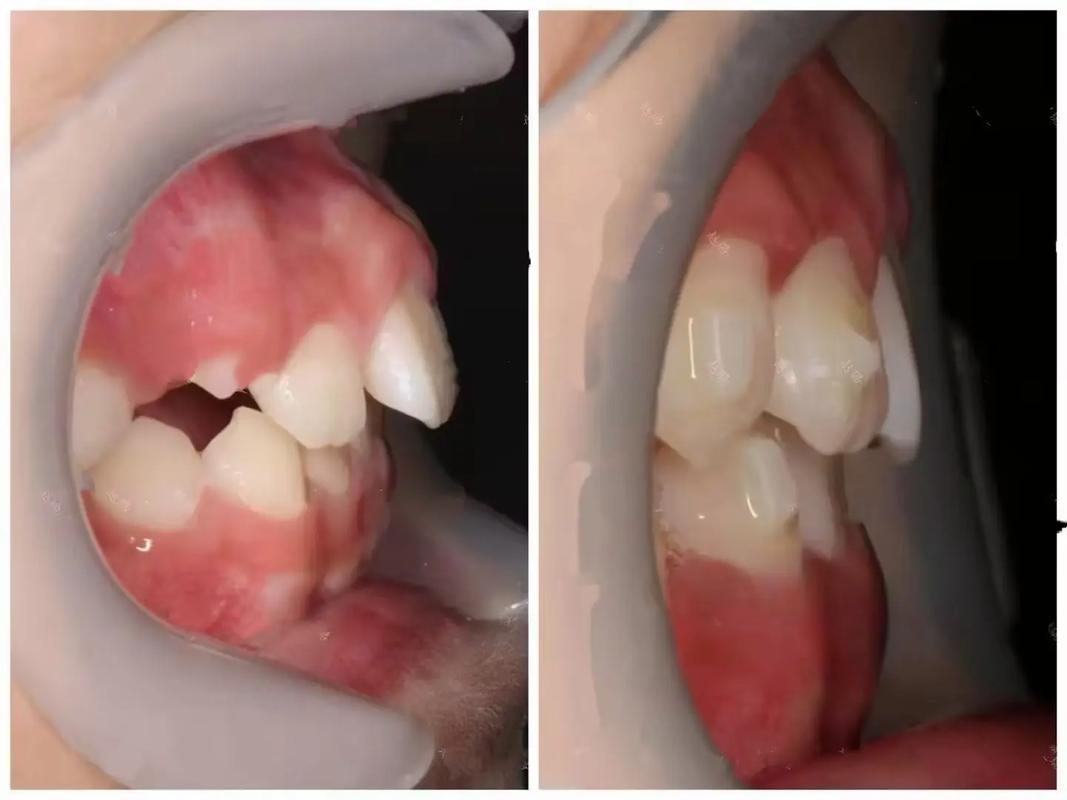

面容外突的牙齿因素主要源于上下颌牙齿过度前倾或牙弓形态异常,导致牙齿在唇侧堆积,形成“凸嘴”外观,矫正牙齿的原理是通过施加持续、轻柔的生物力,引导牙齿在牙槽骨内移动,重新排列牙列,具体而言:

- 牙齿位置调整:将前突的牙齿向舌侧移动,减少对唇部的支撑力,同时后牙可适当前移,建立稳定的咬合关系,使嘴唇能自然贴合,避免因牙齿前突导致的口唇闭合困难。

- 牙弓形态改善:扩缩牙弓,调整牙齿排列的弧度,避免因牙弓过窄导致的牙齿拥挤前突,或牙弓过宽导致的牙齿稀疏,使面部轮廓更流畅。

- 软组织协同改变:牙齿移动会带动牙槽骨改建,进而影响覆盖其上的牙龈、肌肉等软组织,门牙回收后,上唇会因失去过度支撑而内收,鼻唇角(鼻底与上唇的夹角)趋于自然,改善“凸嘴”的突兀感。